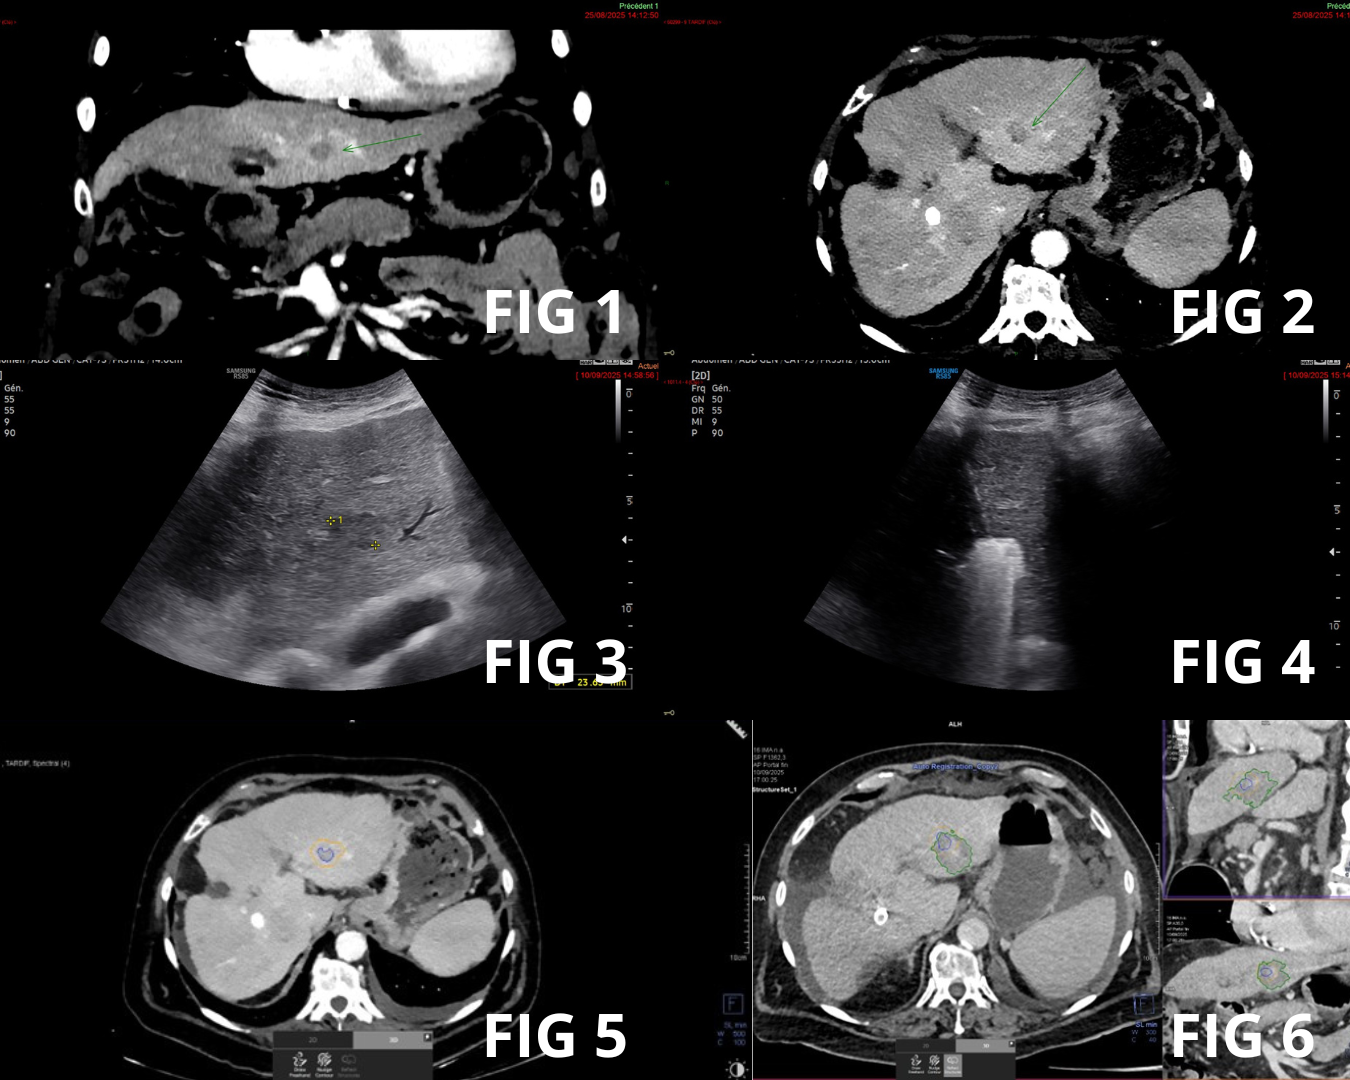

- Traitements mini-invasif des lésions tumorales : traitements intra-artériels, destructions tumorales percutanées